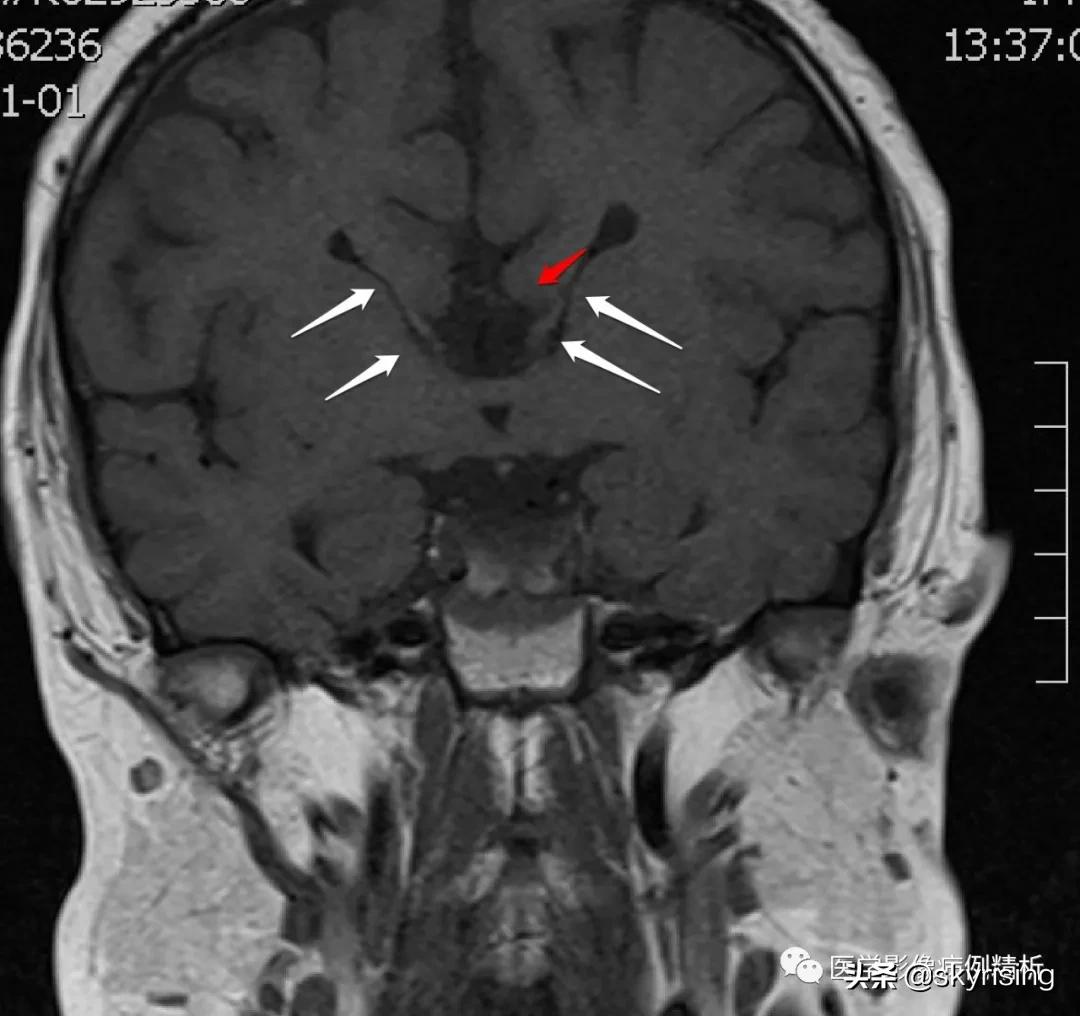

T1WI冠状位如下图所示,红色箭头为扣带回外翻,未能形成扣带沟;白色箭头可见Probst束,沿侧脑室壁向下走行。